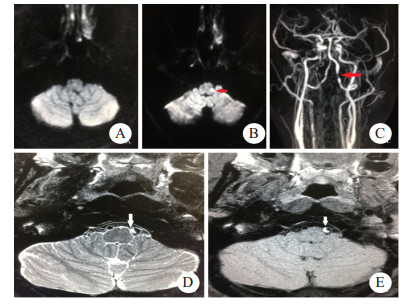

| A:首次头颅DWI检查结果阴性;B:48 h后复查头颅DWI可见左侧延髓背外侧高信号(箭头示);C:颈部血管ceMRA可见左侧椎动脉局部狭窄(箭头示);D、E:高分辨率磁共振可见血管壁间半月形高信号(箭头示) 图 2 例2患者影像学检查结果 |

患者2,男性,53岁,因“突发眩晕3 h”就诊急诊。患者3 h前突发出现眩晕,呈持续性,恶心呕吐,无耳鸣及听力减退,无口齿不清,无口角歪斜,无肢体瘫痪。既往体健,无烟酒史,否认遗传病及传染病,否认外伤及药物滥用。查体:意识清楚,口齿清,两侧瞳孔等大,对光反射存在,双侧眼球向右侧凝视可见水平眼震,向左侧凝视眼震幅度减弱,眼震方向不变,存在固视抑制,鼻唇沟对称,伸舌居中,颈软,心律齐,四肢肌张力正常,四肢肌力Ⅴ级,两侧指鼻试验、跟膝胫试验阴性,感觉检查正常,两侧病理征阴性,左侧甩头试验阳性。辅助检查:血常规、超敏CRP、肝肾功能、血糖、PT、INR、心肌酶谱均正常范围。头颅CT平扫未见明显异常。头颅DWI未见明显异常。急诊诊断前庭神经炎,予以异丙嗪针、甲泼尼龙针、泮托拉唑针治疗。48 h后收入病房,患者眩晕无好转,出现左侧颜面及右侧肢体麻木症状,复查头颅DWI提示延髓梗死,予以阿司匹林、氯吡格雷、阿托伐他汀治疗。进一步完善颈部血管ceMRA可见左侧椎动脉V4段局部狭窄,高分辨磁共振检查可见管壁间亚急性血肿。最终诊断Wallenberg综合征、VAD,经治疗后患者症状好转,出院后服用阿司匹林、阿托伐他汀。门诊随访1年无再发,建议完善脑血管造影检查,患者拒绝。本病例资料的报道已获得患者知情同意。

例2患者无明显脑血管病危险因素,表现为眩晕,无局灶性神经功能缺损,查体可见周围性眼球震颤,床旁头脉冲试验(HIT)左侧阳性,头颅DWI阴性,诊断前庭神经炎,予以甲泼尼龙针抗炎治疗。发病48 h后患者出现感觉障碍,复查头颅DWI可见延髓梗死病灶,改用阿司匹林、氯吡格雷、阿托伐他汀,进一步完善血管检查发现左侧VAD,为病灶责任血管。研究表明,有35%的临床表现类似前庭神经炎的脑卒中患者在急诊被误诊,其中40%的患者病情会进展[10]。Kim等[11]研究认为,局限于前庭神经核或延髓背外侧的小面积梗死可以表现为孤立性眩晕,缺乏异常神经系统症状体征,早期的磁共振检查可呈阴性,患者头脉冲试验阳性,临床表现类似前庭神经炎,容易误诊。该患者早期临床表现类似于前庭神经炎,考虑与病灶局限于前庭神经核及延髓背外侧较小区域有关,直到症状进展出现交叉性感觉障碍,复查头颅DWI,最终确诊。